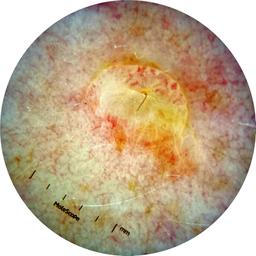

ISIC_7193897

IP_3751325

IL_3780211

Clinical

Field Value

acquisition_day 251

age_approx 65

anatom_site_1 Lower extremity

anatom_site_general lower extremity

concomitant_biopsy False

diagnosis_1 Benign

diagnosis_confirm_type single image expert consensus

family_hx_mm False

image_manipulation instrument only

image_type dermoscopic

lesion_id IL_3780211

patient_id IP_3751325

personal_hx_mm True

sex female